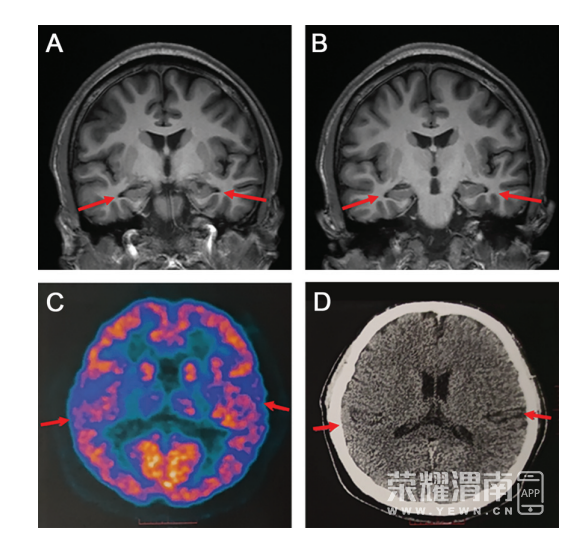

贾龙飞介绍,PET扫描和脑脊液指标检查,以及多种量表检测可以相辅相成,互相印证,以此才可以做出准确的临床诊断。